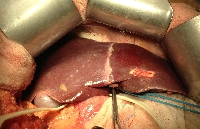

Πρόκειται για γυναίκα ασθενή 55 ετών η οποία είχε υποβληθεί σε σιγμοειδεκτομή και μετεγχειρητική χημειοθεραπεία για αδενοκαρκίνωμα του παχέος εντέρου (Τ3Ν1). Ένα έτος μετά τη σιγμοειδεκτομή, κατά τον τακτικό απεικονιστικό έλεγχο (MDCT), αναγνωρίστηκε μονήρης μεταστατική εστία στη μετάπτωση των ηπατικών τμημάτων 3 & 4b. Υποβλήθηκε εκ νέου σε χημειοθεραπεία (neoadjuvant) 6 κύκλων. Το διεγχειρητικό υπερηχογράφημα δεν ανέδειξε άλλες, πλην της ήδη γνωστής, ηπατικές μεταστάσεις (εικόνα 1). Ύστερα από ηπατική κινητοποίηση (εικόνα 2), υποβλήθηκε σε αριστερή ηπατεκτομή (εικόνες 3 & 4), με διατήρηση του κερκοφόρου λοβού (κλάδος PV1). Το ηπατικό υπόλειμμα φαίνεται στην εικόνα 5. Η ασθενής έλαβε εξιτήριο την 6η μετεγχειρητική ημέρα. Η χημειοθεραπεία (adjuvant) θα ολοκληρωθεί με άλλους 6 κύκλους.